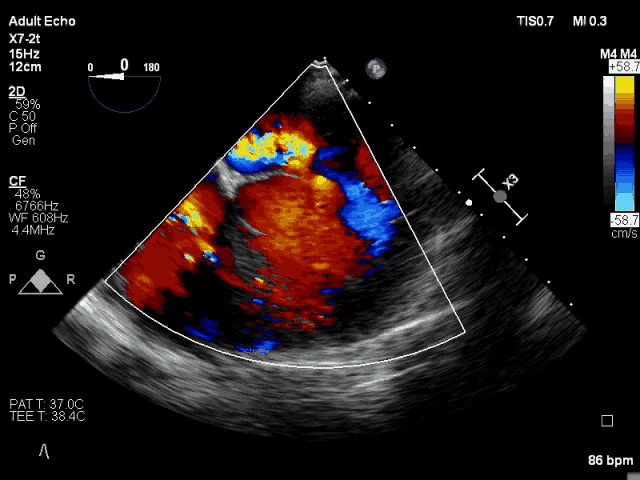

术前TEE CDFI示MR重度

此次手术直播患者为86岁老年女性,体重仅40Kg,二尖瓣后叶P2和P’1脱垂,极重度二尖瓣反流,同时合并重度肺动脉高压、中重度三尖瓣反流,STS评分11.05%,外科手术非常高危。患者二尖瓣后叶主腱索断裂,连枷锁间隙大,使用国外同类器械可能难以完成手术。